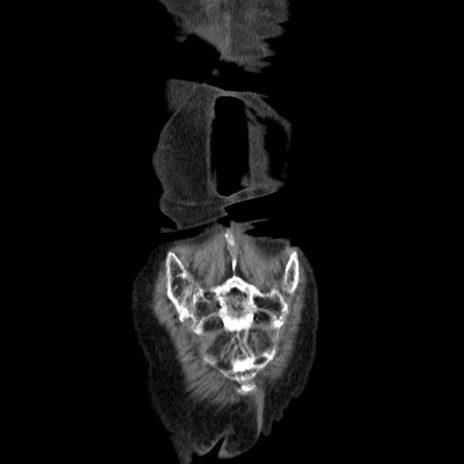

横断像